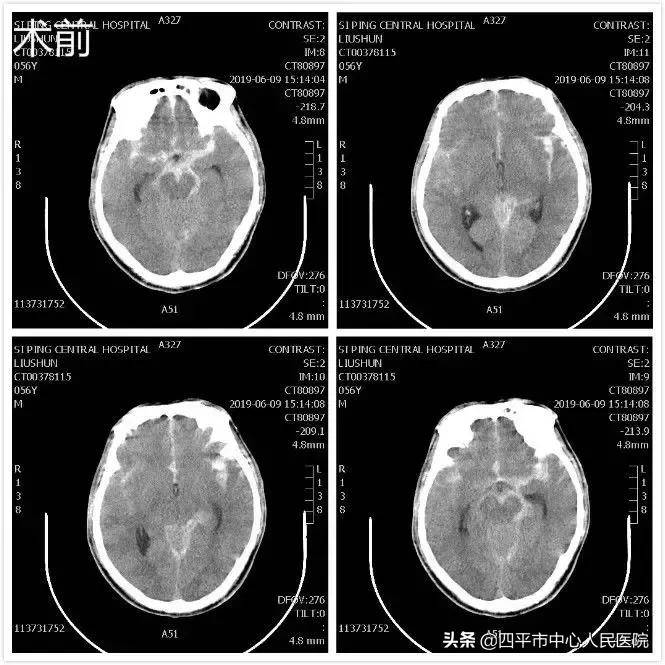

Case1 左侧颈内动脉末端囊状动脉瘤

患者刘XX,缘于入院前2小时无明显诱因在劳动时突发意识不清,从2米高处坠落,既往身体健康,入院头部CT提示蛛网膜下腔出血,李晓东主任阅头部CT片后指示该患者应该是先脑出血而后摔倒,不能除外动脉瘤破裂,入院后完善头部CTA检查,提示1.左侧颈内动脉末端动脉瘤。2.左侧大脑中动脉闭塞。3.双侧颈内动脉颅内段轻度狭窄。4.脑内动脉粥样硬化改变。5.右侧胚胎型大脑后动脉。李晓东主任带领孙庆华急诊全麻下行左侧颈内动脉末端动脉瘤夹闭术,术中注意避免误夹后交通动脉,否则造成的后果是灾难性的,经术中仔细操作,确切夹闭动脉瘤,术中顺利,术后患者病情逐渐好转,出院时神清语明,四肢肌力5级,送来锦旗表示感谢。